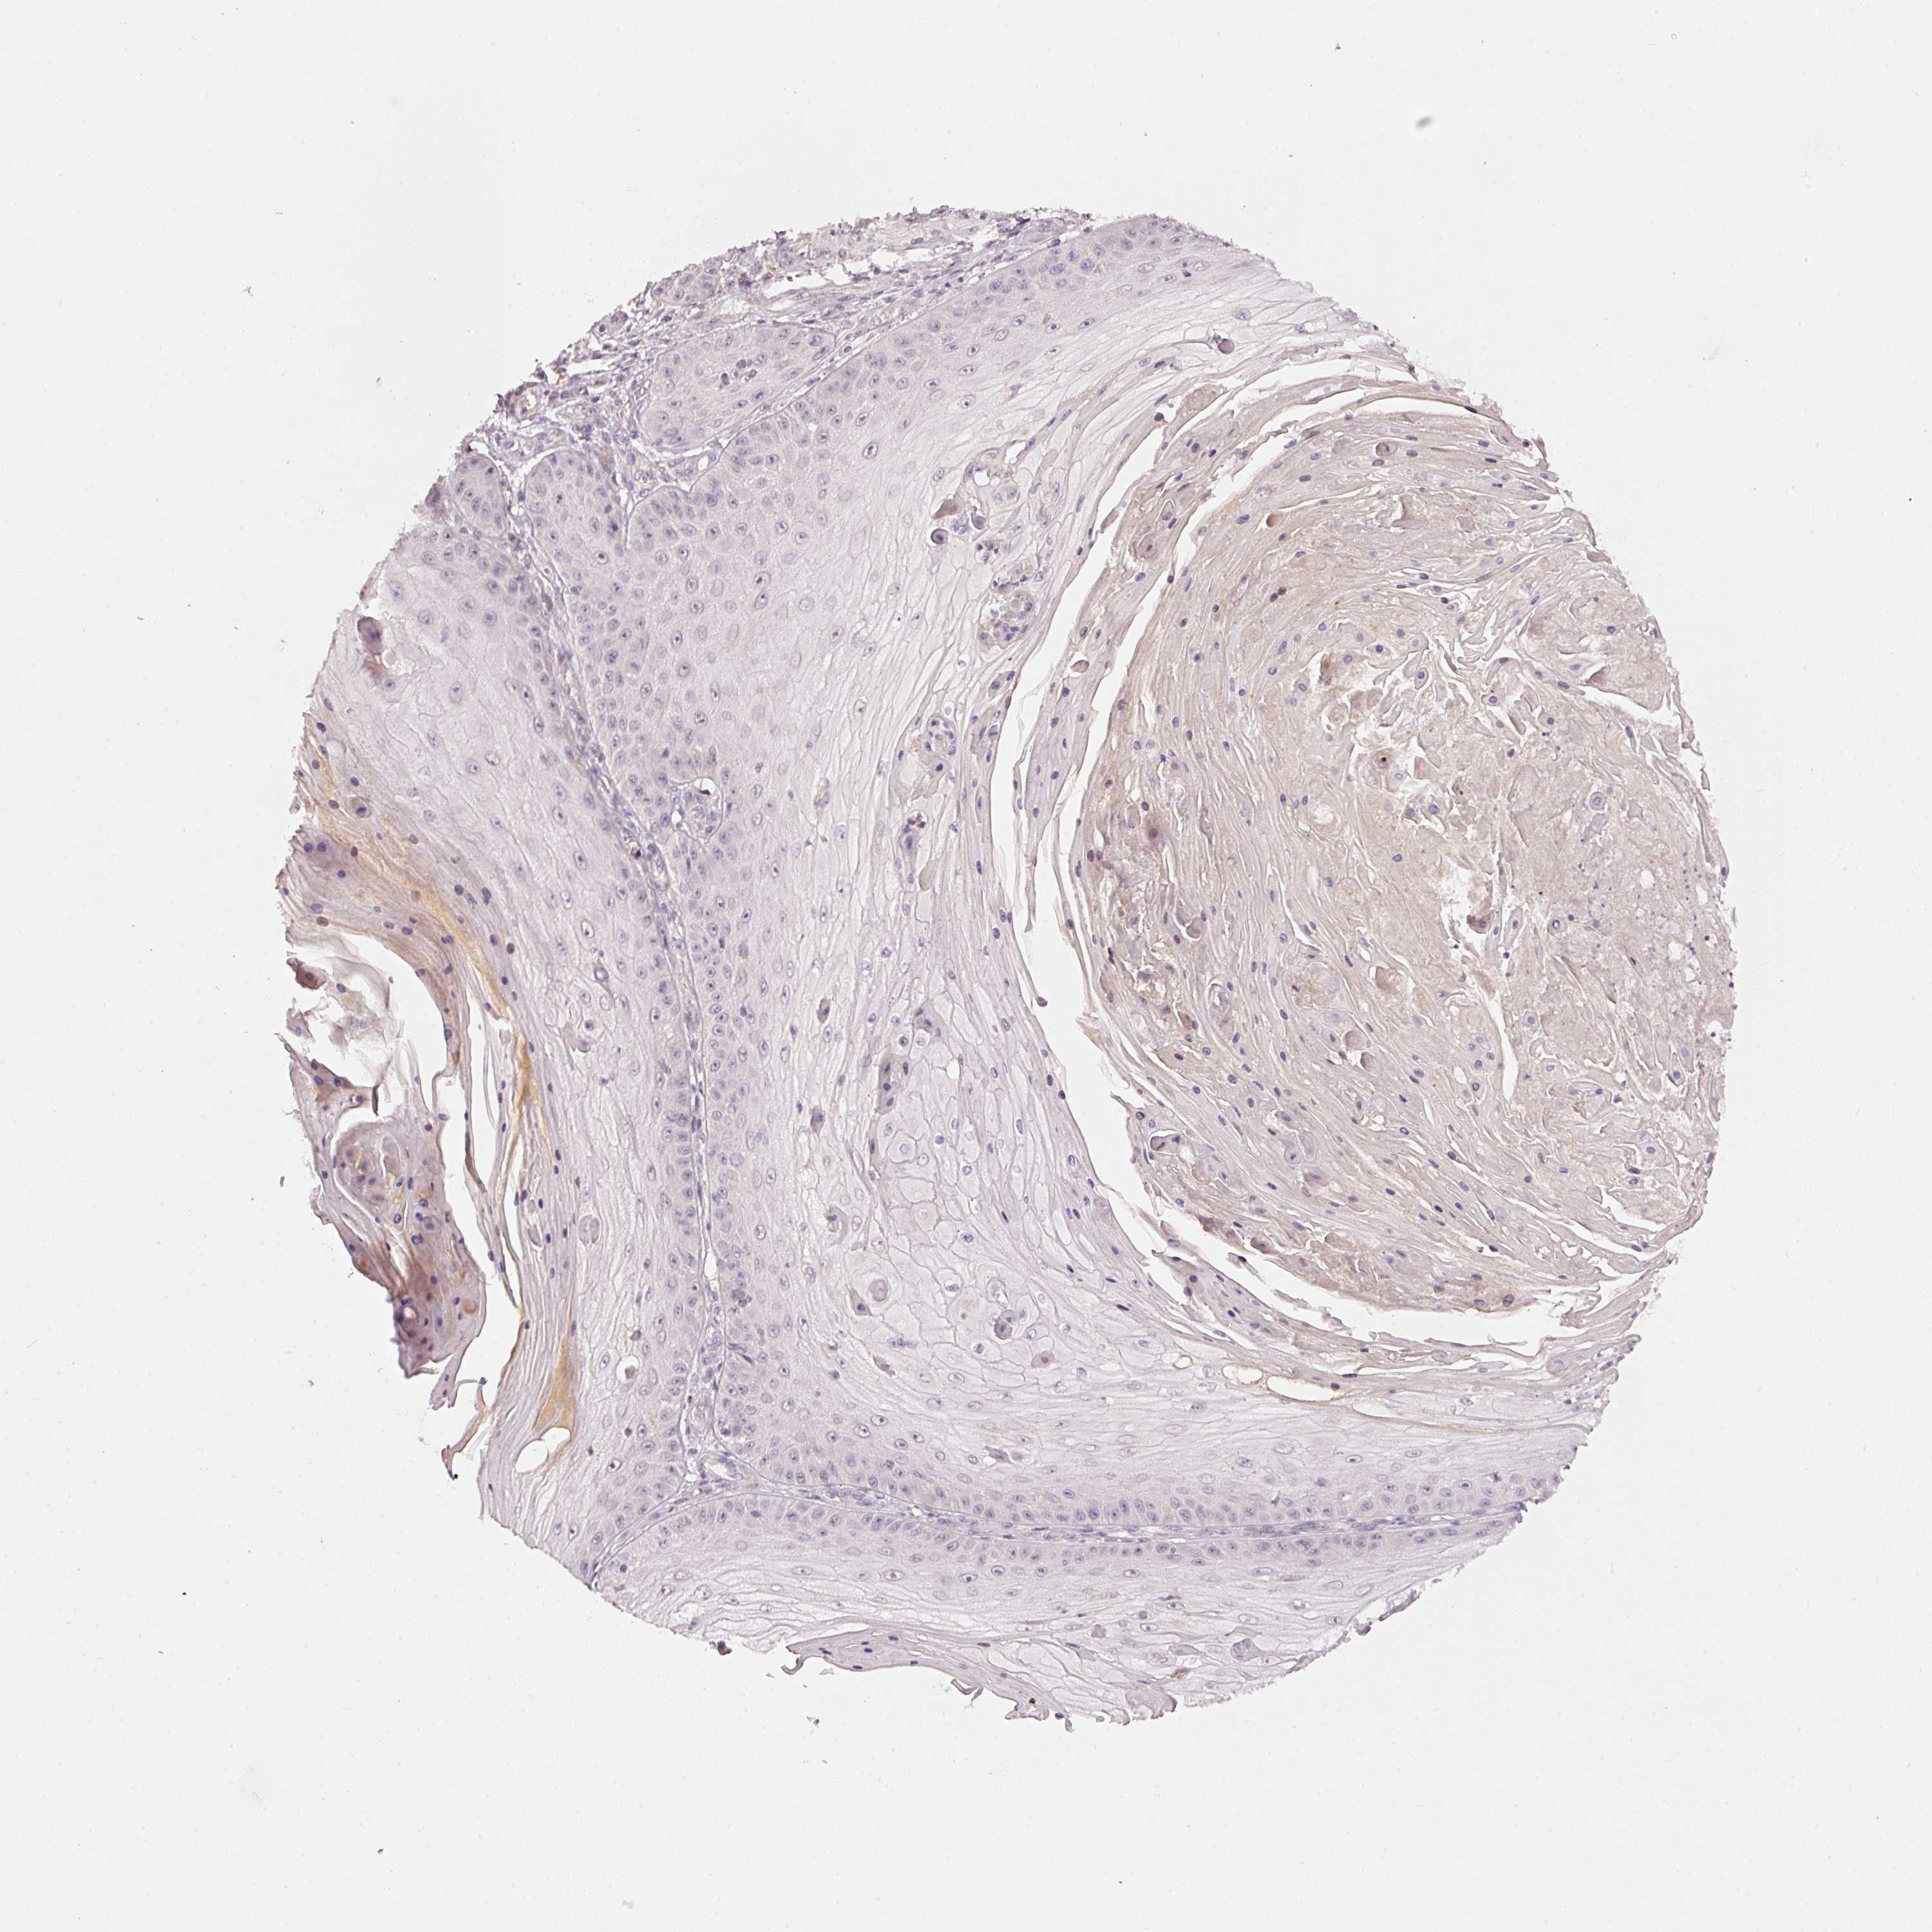

SKIN CANCER - Protein expressioni

A mouse-over function shows sample information and annotation data. Click on an image to view it in a full screen mode. Samples can be filtered based on level of antibody staining by selecting one or several of the following categories: high, medium, low and not detected. The assay and annotation is described here.

Antibody staining in the annotated cell types in the current human tissue is reported as not detected, low, medium, or high, based on conventional immunohistochemistry profiling in selected tissues. This score is based on the combination of the staining intensity and fraction of stained cells.

Each image is clickable and will lead to virtual microscopy that enables deeper exploration of all samples and also displays staining intensity scores, fraction scores and subcellular localization as well as patient and tissue information for each sample.

Antibody HPA054112

Staining

High

Medium

Low

Not detected

Intensity

Strong

Moderate

Weak

Negative

Quantity

>75%

75%-25%

<25%

None

Location

Nuclear

Cytoplasmic/membranous

Cytoplasmic/membranous,nuclear

Basal cell carcinoma

Squamous cell carcinoma, NOS